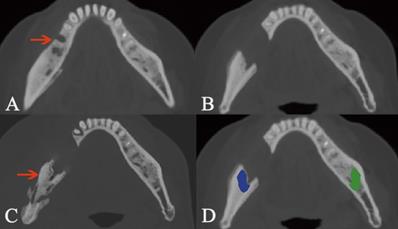

Osteosclerotic lesion and its transformation to osteolytic lesion. The lesion is pointed out by the arrow in intraoral photograph (A) and axial plane (B). Due to the lesion was located at two areas including AR and BR, the segmentation boundary was set from the mandibular symphysis to the anterior of ramus (C, D, E). The segmentation of cancellous bone in sclerotic lesion is colored as blue, while the same area in the bilateral side is segmented as the control and colored as green. The transformation from osteosclerotic lesion to osteolytic lesion is presented (F).

In this study, we focused on the trabecular changes in cancellous bone and classified the MRONJ lesions into two types, including osteosclerotic and osteolytic lesions (Fig. 1A, B; Fig. 2A, B). We defined osteosclerotic lesions as the increased alveolar bone density without any other trabecular changes. Once osteolysis occurs, the radiographic type of MRONJ lesions was classified as osteolytic lesions. The osteosclerotic lesion only presented as sclerosis in CT imaging, while the osteolytic lesion could involve many CT imaging features, such as osteolysis, sequestrum and sclerosis. The defined MRONJ lesions in radiography were depicted in Figure 3.

In this study, the transformation from osteosclerotic lesions into osteolytic lesions was do observed in many MRONJ patient. Among those patients, we measured the radiodensity values of osteosclerosis which was the initial manifestation in radiography and recorded the transformation from osteosclerotic lesions to osteolytic lesions. Additionally, post-surgical recurrences and the radiodensity values around the post-surgical lesions were recorded as well.